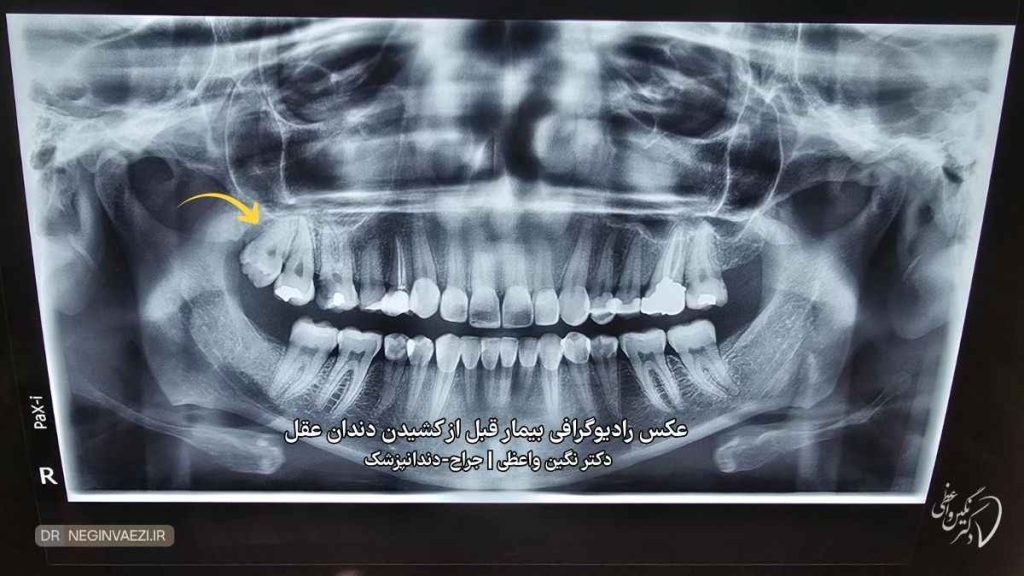

در این نمونه درمان انجام شده، عکس قبل و بعد کشیدن دندان عقل رو بدون درد و بخیه مشاهده می کنید.بیمار با شکایت درد و فشار روی لثه در هنگام غذا خوردن به مطب دکتر نگین واعظی مراجعه کردند. برای بیمار رادیوگرافی پانورامیک (OPG) تجویز شد و پس از آن طی بی حسی موضعی و بدون درد و جراحی ، دندان عقل بالا راست بیمار کشیده شد. در ادامه شما می توانید رادیوگرافی و عکس دندان عقل خارج شده رو مشاهده کنید.

عکس رادیوگرافی پانورامیک قبل از کشیدن